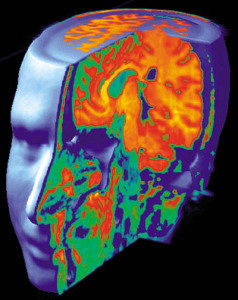

Dr. Jill Bolte Taylor, Ph.D, is a Neuro-Anatomist who was trained at Harvard Medical School. Her specialty is in the postmortem investigation of the human brain as it relates to schizophrenia and the other severe mental illnesses.

Dr. Jill Bolte Taylor, Ph.D, is a Neuro-Anatomist who was trained at Harvard Medical School. Her specialty is in the postmortem investigation of the human brain as it relates to schizophrenia and the other severe mental illnesses.

In her book, titled My Stroke of Insight, she writes about her experiences in 1996, while suffering a form of arterio-venous malformation stroke, which allowed her the rare privilege of being able to study a stroke as it was actually occurring. During this stroke, she was able to watch as her own brain functions shut down, one by one – her ability to walk, talk, read and write.

The swelling and trauma of the stroke placed pressure on the dominant left hemisphere of Dr. Taylor’s brain. As a result, she was unable to recall any part of her life. But, in the absence of the neural circuitry of her left hemisphere, her consciousness shifted into the present moment. This was when the functions of her right hemisphere increased. Her right hemisphere left her feeling expansive, totally at peace in the Universe and connected as part of it.

Dr. Taylor was forced to undergo major brain surgery to remove a large blood clot that was putting pressure on her language centers. Although the stroke damaged the left side of her brain, her recovery burst forth an avalanche of creative energy from the right side.[i] She now travels the country educating audiences about the beauty of the brain. In 2008, she was chosen as one of TIME Magazine’s 100 Most Influential People in the World.

The left hemisphere is the side that is concerned only with our human condition. It understands logic, mathematics, sequential relation-ships and the parasympa-thetic nervous system. Its main job is to place everything in this reality into a Time line. This creates the illusion that we are finite, that we are separate from one another and separate from God.

The left hemisphere is the side that is concerned only with our human condition. It understands logic, mathematics, sequential relation-ships and the parasympa-thetic nervous system. Its main job is to place everything in this reality into a Time line. This creates the illusion that we are finite, that we are separate from one another and separate from God.

In contrast, the right hemisphere of the brain is the side that represents the creative part of the human biology. This includes music, rhythm, imagination, intuition, humor, dreams and the sympathetic nervous system. The right hemisphere understands that we are infinite, connected in unity to one another and to God.